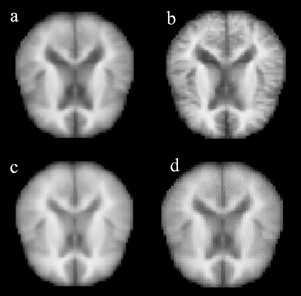

(Figure 8) depicts the average MRI scans for various dementia stages, showing a gradual intensity increase in the cerebral cortex region from no dementia to moderate dementia. This pattern is a promising identifier for training the vision transformer.

Figure 8. (a) Mild Dementia (b) Moderate Dementia (c) No Dementia (d) Very mild Dementia.